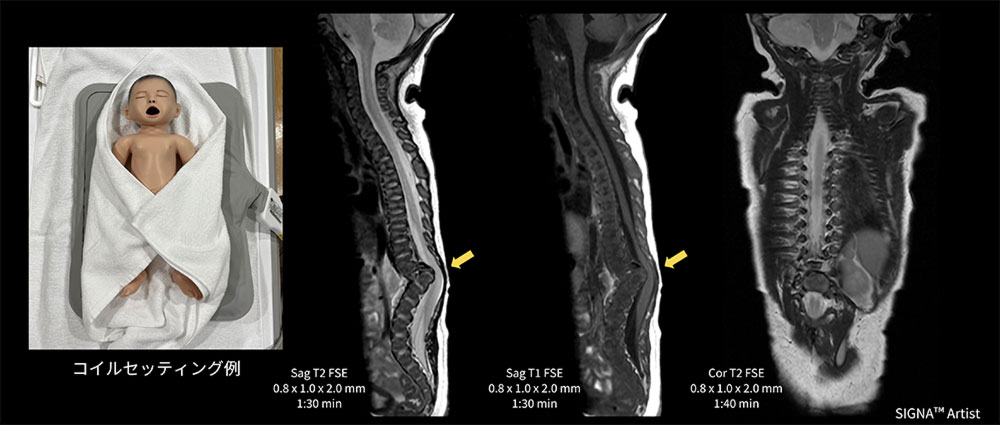

Case3 新生児の脊椎検査

生後7日の新生児。出生前MRI検査時に脊椎異常を指摘されており、出生後に脊椎MRI検査を実施。

Spineコイルや従来からあるGEM Flex Coilを検討したが、対象が小さい事やコイルの硬さ、また体動や固定が懸念された。MP Coil自体クッション性があるので、MP Coilの上に仰臥位のポジショニングで、固定も問題なく検査が施行できた(図5)。Th10~L1は分離不能で急峻な後湾変形を認め、脊柱管はこの上下で狭小化。脊髄空洞症や脂肪腫は認めず分節性脊椎形成異常症と診断された一例。

AirCoils_Shigaikadai_06.jpg図5 新生児の脊椎検査におけるMP Coilのセッティング例と臨床画像